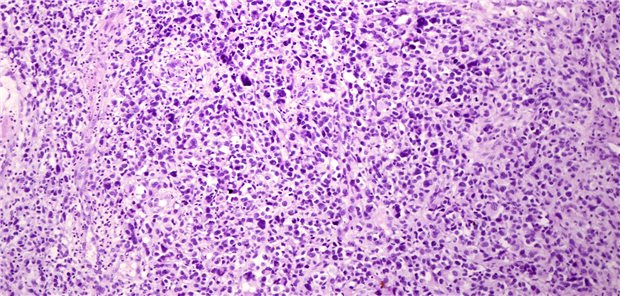

Innerhalb einer Phase-II-Studie zeigte sich die Wirksamkeit von VEGFR-Inhibitoren bei verschiedenen histologischen Sarkom-Subtypen.

© JOSE CALVO / Science Photo Library

In der SNP-Kohorte mit 27 Patienten wurde der primäre Endpunkt erreicht, mit einer PFR-Rate nach 16 Wochen von 74 Prozent versus 42,3 prozent in der unselektierten Kontrollgruppe. Das mediane progressionsfreie Überleben (PFS) betrug 6,0 Monate versus 3,9 Monate. Die Wirksamkeit zeigte sich bei verschiedenen histologischen Sarkom-Subtypen.